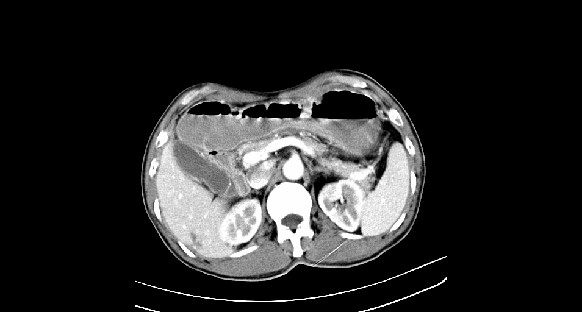

男性,70岁,体检b超发现左肾占位,请各位战友发表一下观点

左肾有两个病灶,且较大的病灶内可见点状钙化灶,增强扫描边缘也是呈渐进性强化,中央部分未见明显强化